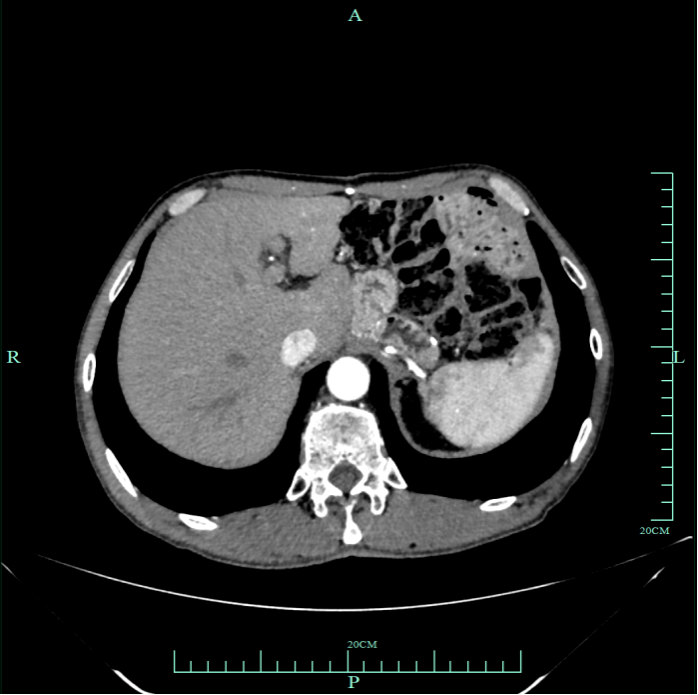

930.4.png

图2 复查CT结果

·术后病理:送检组织未见明确肿瘤成分残留,达到pCR。肿瘤退缩分级(TRG评分)为TRG 0级,Becker分级为Grade 1a。